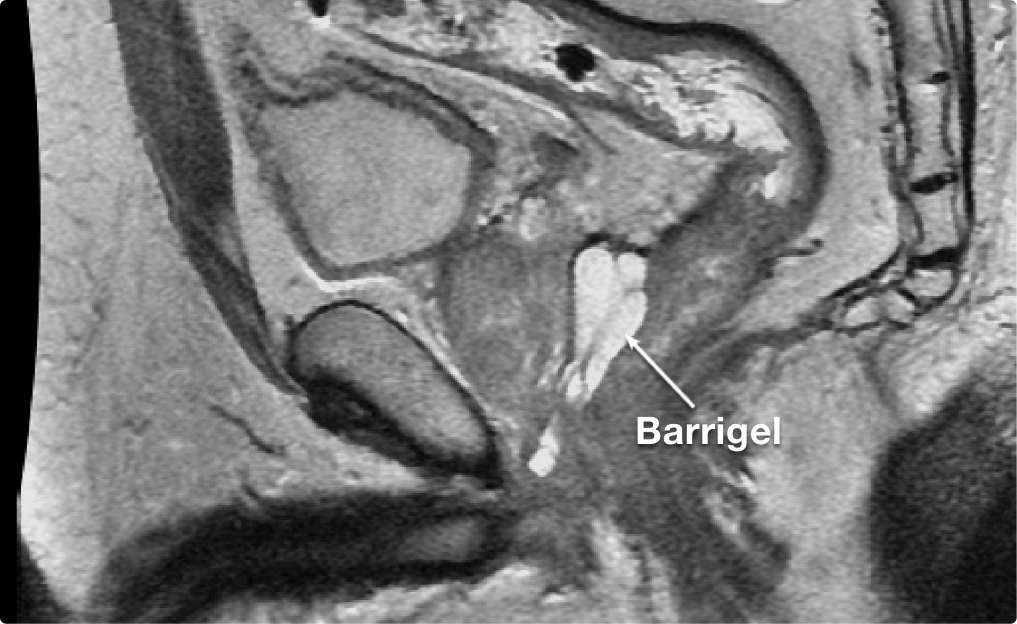

左右対称なスペーシング

均一なカバレッジを実現します。Barrigel のPivotal試験では、95%以上のインプラントが正中線上に留

置されました2。

* BarrigelのPivotal試験のデータは、Fischer-Valuck試験と同じ手法で解析した。